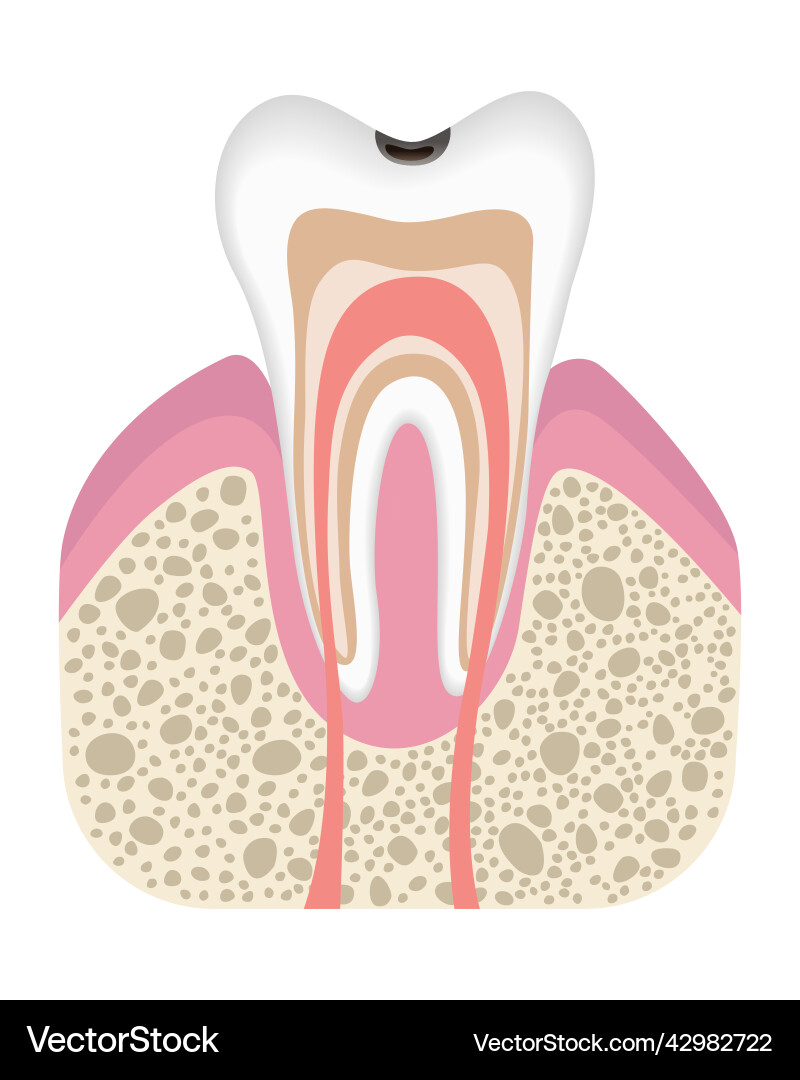

- Image ID

- 42982722

- Artist

- Designer_things

- Caries

- Tooth

- Structure

- Decay

- Enamel

- Anatomy

- Dentin

- Pulp

- Molar

- Root